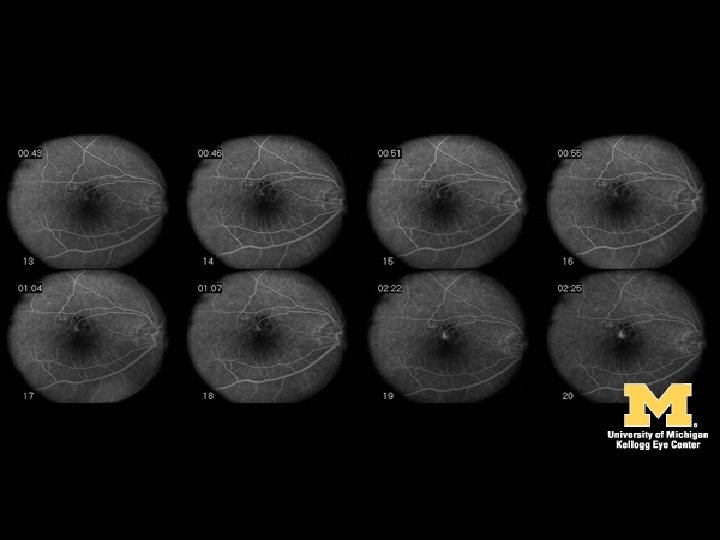

THE PICTURE AND FLUORESCEIN ANGIOGRAPHY ARE TAKEN FROM A PATIENT COMPLAINING OF DISTORTED RIGHT

THE PICTURE AND FLUORESCEIN ANGIOGRAPHY ARE TAKEN FROM A PATIENT COMPLAINING OF DISTORTED RIGHT VISION. A. WHAT PHASE IS THE FLUORESCEIN ANGIOGRAPHY? B. WHAT IS THE DIAGNOSIS? C. WHAT UNDERLYING MEDICAL CONDITION

• Venous phase • Macroaneurysm • Hypertention